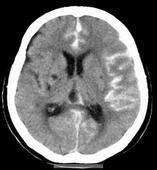

自发性蛛网膜下腔出血

628健康网为您分享有关自发性蛛网膜下腔出血的症状,自发性蛛网膜下腔出血的治疗方法,自发性蛛网膜下腔出血的预防知识...

自发性脑室内出血

628健康网为您分享有关自发性脑室内出血的症状,自发性脑室内出血的治疗方法,自发性脑室内出血的预防知识,自发性脑室内出...

高血压性脑出血

628健康网为您分享有关高血压性脑出血的症状,高血压性脑出血的治疗方法,高血压性脑出血的预防知识,高血压性脑出血的症状...

迟发性外伤性脑内血肿

628健康网为您分享有关迟发性外伤性脑内血肿的症状,迟发性外伤性脑内血肿的治疗方法,迟发性外伤性脑内血肿的预防知识...